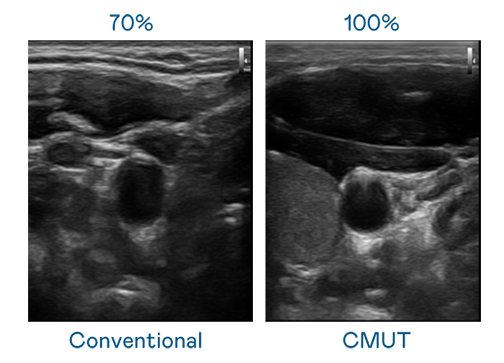

CMUT 技術是一種用電容式微機電元件來產生超音波訊號的技術。與傳統 PZT 壓電式技術相比,CMUT 頻寬增加 30%,更寬頻的超音波訊號讓影像解析度大幅提升,是實現高影像品質醫療超音波掃描、促進精準醫療發展的關鍵技術。

超音波影像的解析度高低,首先取決於探頭能發出的訊號頻寬。918博天娱乐 CMUT 可提供高清晰的超音波訊號,提供高頻寬、高靈敏度、影像紋理細節更高的超音波影像,協助醫護人員縮短影像判讀時間及利用精準的醫療影像進行診斷。